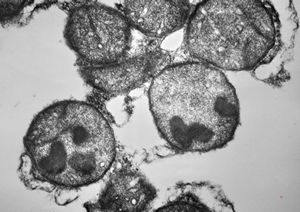

M,11y. | mast cell - skin

M,3y. | mast cell - n. suralis, Krabbe globoid leukodystrophy

F,23y. | mast cell - n. suralis, demyelinating neuropathy